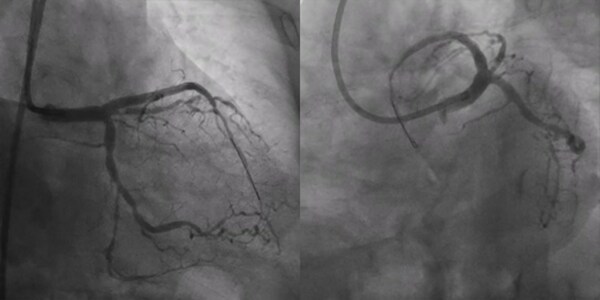

術(shù)前冠脈造影:

造影顯示中間支近段90%狹窄,LAD齊口完全閉塞,RCA近中段管腔不規(guī)則,最狹窄處80%,可見明顯側(cè)枝。

最終結(jié)果:

造影顯示TIMI 3級(jí)血流,支架擴(kuò)張充分,IVUS顯示支架貼壁良好,遠(yuǎn)段無(wú)并發(fā)癥,手術(shù)成功?;颊呤中g(shù)當(dāng)天順利出院,便可恢復(fù)正常生活和工作。

最終造影